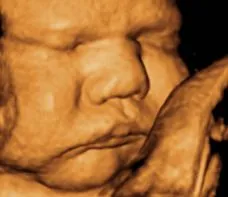

How about this, according to the soulless Democrat goons, this is nothing but a sack of cells that can be murdered at any time, if the mother so wishes.